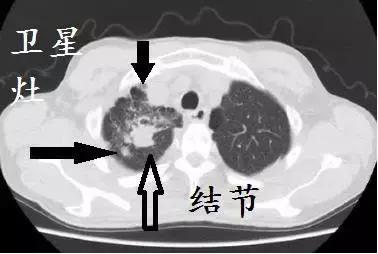

肺结核的图片大全ct,空洞型肺结核ct图片

图6 继发性结核分枝杆菌感染轴位ct 图像显示左肺上叶尖后段空洞(大

空洞型肺结核ct图片

肺结核CT空洞